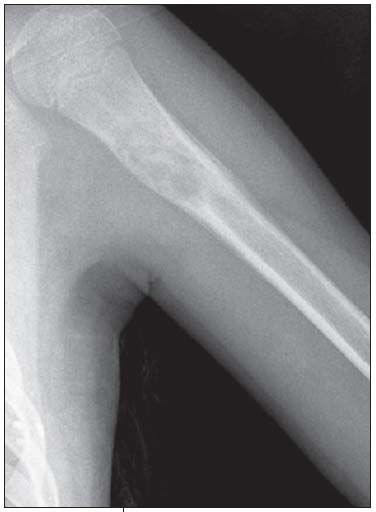

Anteroposterior and lateral views of the patient's left humerus were ordered.

The radiographs show a centrally placed lytic lesion with lobulated contours and a well-defined transition zone in the proximal shaft of the humerus. An oblique pathological fracture runs through the cyst No other lesions are visible. A thick periosteal reaction on the medial aspect of the lytic lesion is also present; the periosteal reaction is atypical in this case; however, the radiographs were obtained 10 days after the fall.

This is a unicameral, or simple, bone cyst. Many of the lesions in the differential diagnosis, including aneurysmal bone cyst, osteomyelitis, malignant lytic lesion (such as eosinophilic granuloma or bone metastasis), can be excluded on the basis of location. The location of simple bone cysts is usually the humeral head, ball of the foot, proximal femur, or proximal humerus or calcaneus.

A simple bone cyst may be an incidental finding. However, like this child, most patients present with a pathological fracture. The pathognomonic sign after a fracture is a fallen fragment in the most dependent portion of the cyst. Occasionally, a periosteal reaction can be seen. A simple bone cyst is a fluid-filled cavity lined with fibrous tissue. It is thought to result from venous outflow obstruction, which leads to an increased intraosseous pressure and a consequent stimulation of

osteoclastic activity. This benign lesion usually devel-ops within the first 2 decades of life. The cyst causes bone instability and sometimes may be associated with pathological fractures after relatively minor trauma.